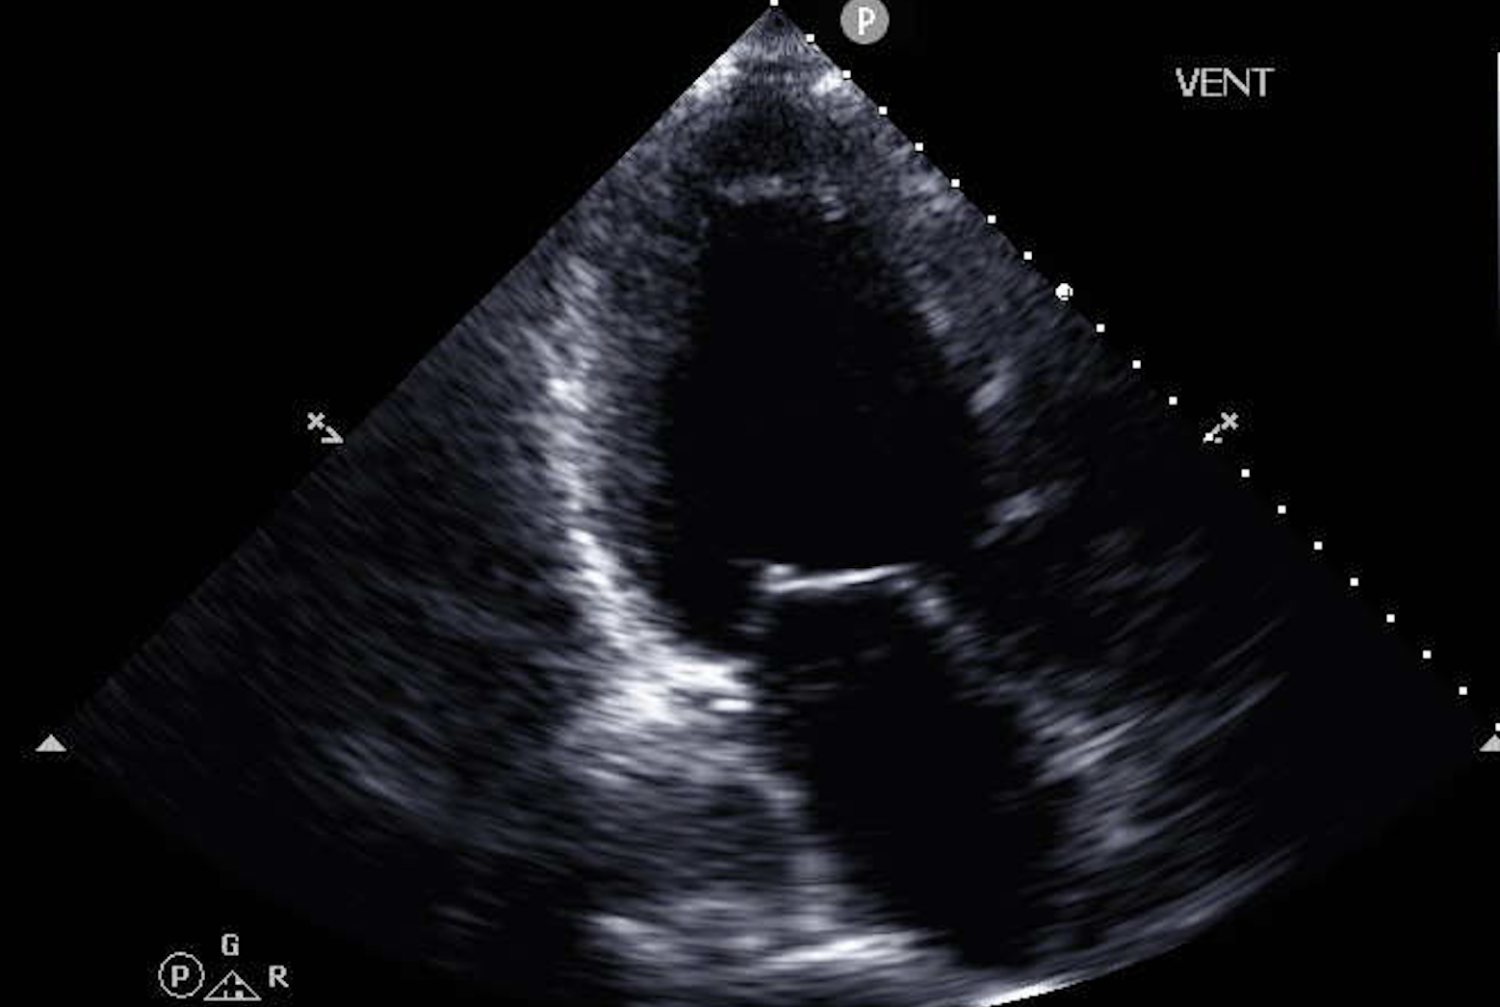

Heart ultrasounds, known as echocardiograms, are routine. Nearly every cardiology practice uses them. On their own, though, standard echocardiograms have not proven to be strong predictors of survival outcomes in heart failure, partly because the most important information is often buried across multiple image types rather than visible in any single measurement.

The team asked whether a machine learning model could do what human reviewers often can’t, which is to detect patterns across many simultaneous data streams and integrate them with clinical context. They built a system that analyzes several categories of ultrasound data together: moving video images of the heart’s chambers, valve motion patterns, and Doppler signals measuring blood flow. Those imaging inputs were combined with information pulled from electronic health records, including patient age, body mass index, and standard clinical measurements.